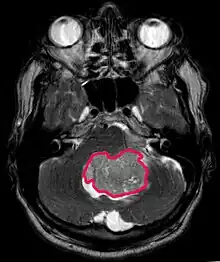

Le médulloblastome est la tumeur cérébrale maligne la plus fréquente chez l'enfant. L'incidence la plus élevée survient chez les enfants âgés de 2 à 7 ans. Le plus grand risque de maladie demeure dans l'enfance, car le médulloblastome est très rare chez les personnes de plus de 21 ans.

Cette tumeur est typique de la fosse postérieure, où elle est localisée dans les deux hémisphères du cervelet ou dans le vermis cérébelleux. Parce qu'il est envahissant et à croissance rapide, il se propage généralement à d'autres parties du système nerveux central (SNC) via le LCR et peut infiltrer le plancher du quatrième ventricule voisin et les méninges. Plus rarement, des métastases supplémentaires du SNC peuvent survenir. Lorsque la tumeur maligne survient, les symptômes comprennent la perte d'équilibre, l'incoordination, la diplopie, la dysarthrie et l'atteinte du quatrième ventricule, ce qui entraîne souvent une hydrocéphalie obstructive, des maux de tête, des nausées et des vomissements et une démarche instable.

L'IRM montre généralement une lésion de contraste massive impliquant le cervelet. Comme mentionné ci-dessus, le médulloblastome a une forte propension à infiltrer localement les leptoméninges ainsi qu'à se propager à travers l'espace sous-arachnoïdien, impliquant les ventricules, la convexité cérébrale et les surfaces leptoméningées de la colonne vertébrale. Par conséquent, il est nécessaire de mettre en résonance tout l'axe crânio-spinal.

Le but de la chirurgie est d'enlever autant que possible la masse présentée par la lésion. En effet, les tumeurs résiduelles postopératoires entraînent un moins bon pronostic. La présence de cellules tumorales dans le liquide céphalo-rachidien ou la détection par résonance de métastases leptoméningées est également un signe avant-coureur d'un pronostic défavorable. La chirurgie seule n'est généralement pas curative. Dans certains cas, cependant, une irradiation thérapeutique de l'axe craniospinal, focalisée sur le site tumoral primaire, peut en résulter. L'ajout d'une chimiothérapie après la radiothérapie augmente le taux de guérison. Des médicaments à base de platine (cisplatine ou carboplatine), de l'étoposide et un agent alkylant (cyclophosphamide ou lomustine) sont utilisés avec la vincristine. Avec un traitement approprié, les cas de longue survie de plus de 3 ans chez les patients atteints de médulloblastome varient de 60 à 60 ans et 80 Pour cent.